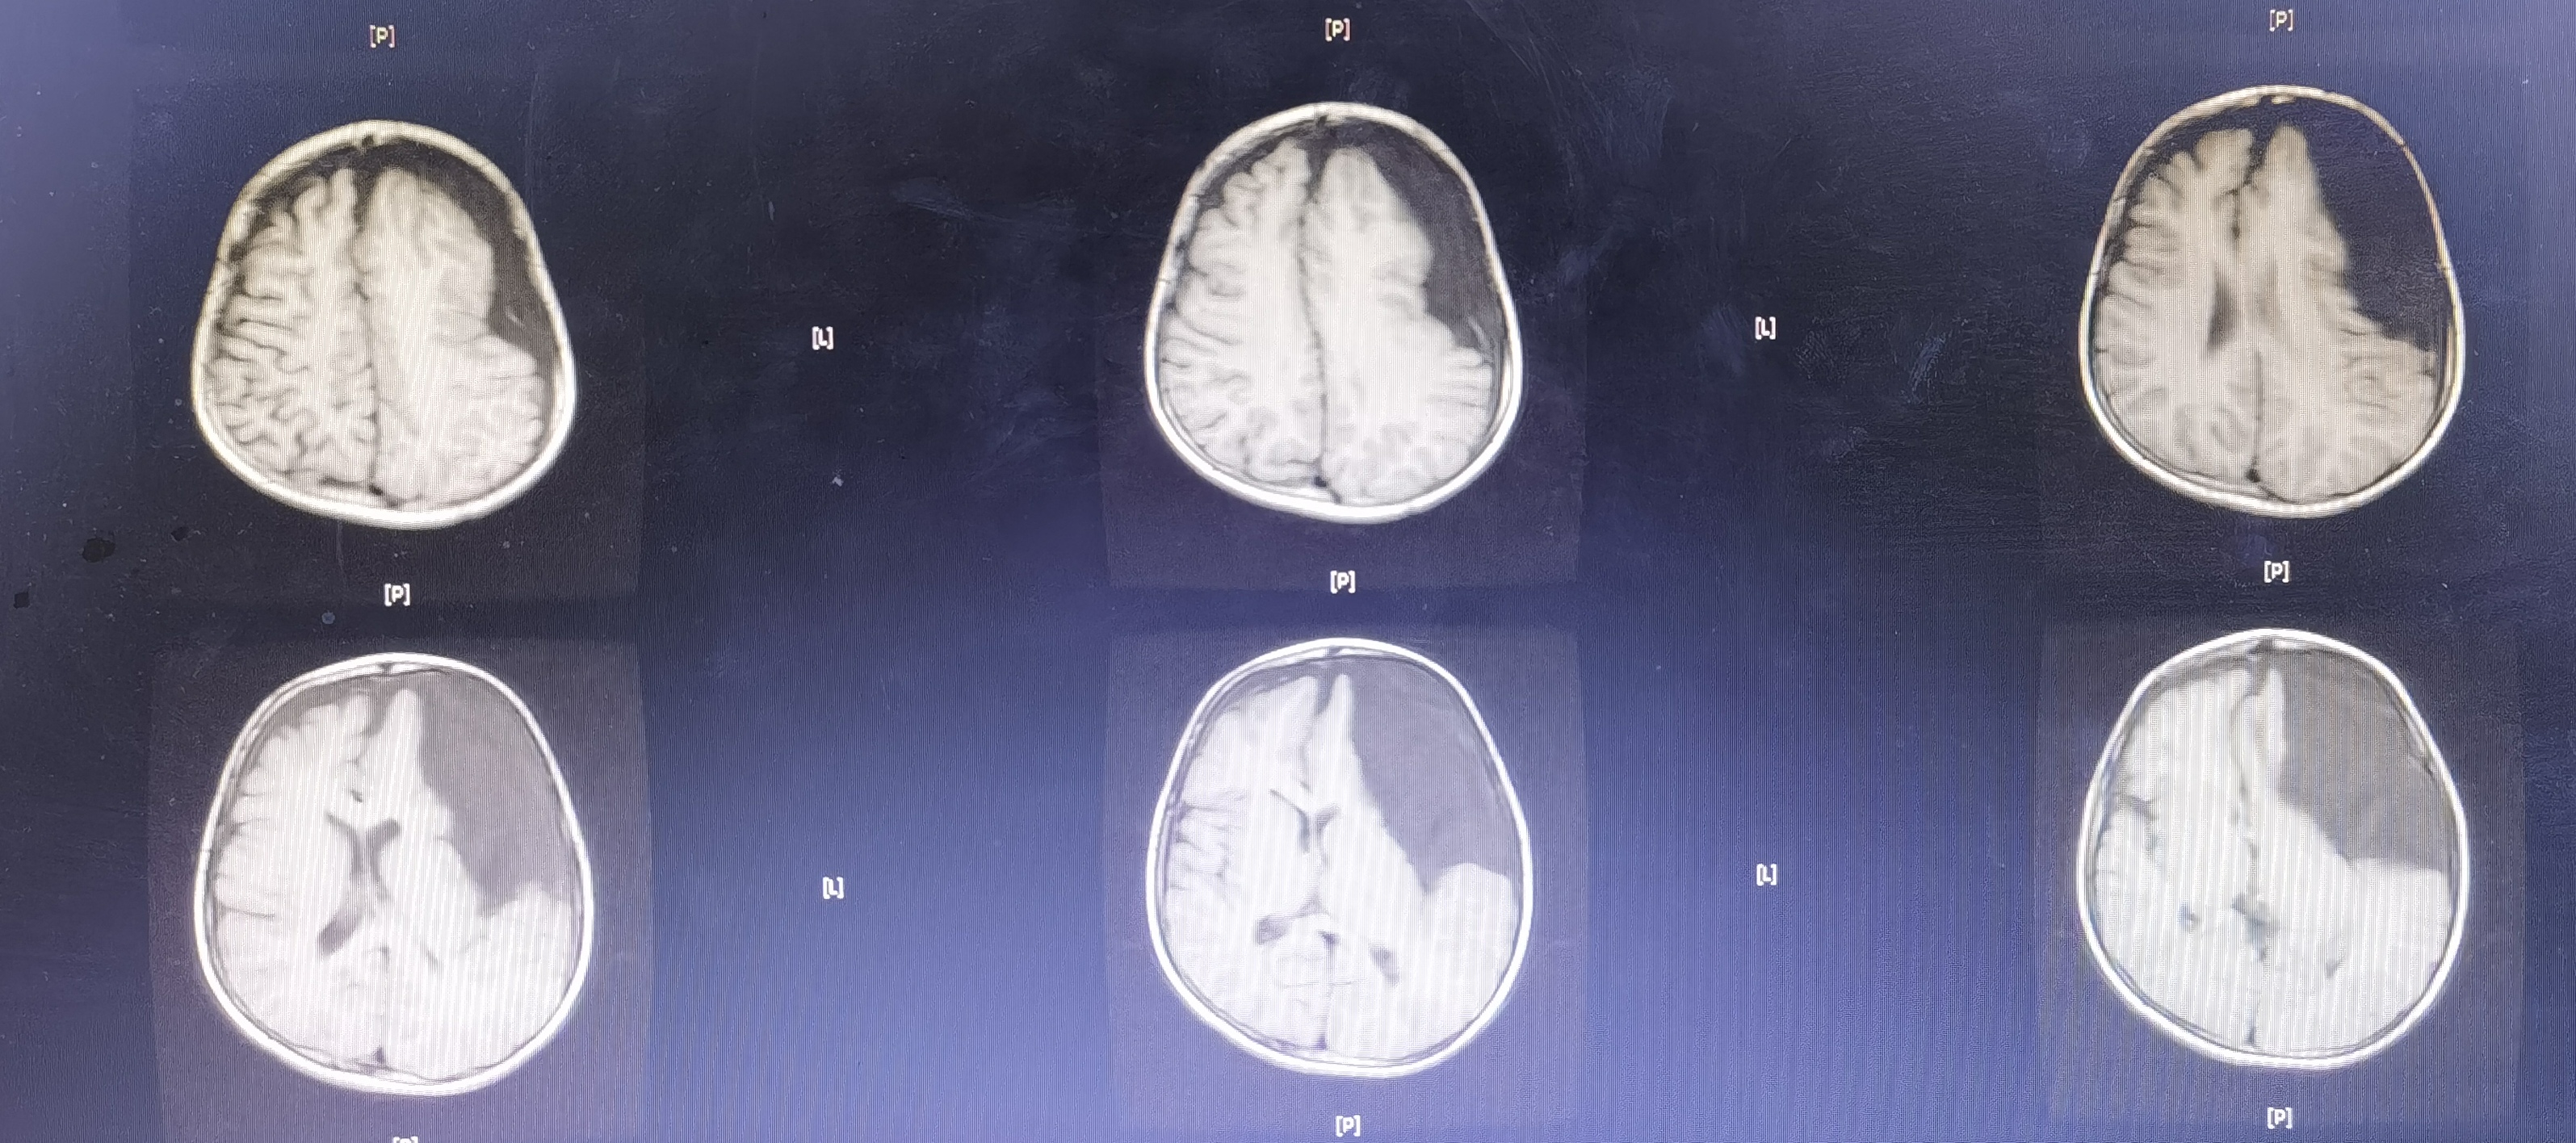

8岁男孩,以“头部外伤后头晕8天”入院,患儿8天前于3米高处坠落摔伤头部,伤后有昏迷史,当地医院CT提示左额颞巨大蛛网膜囊肿,破裂可能。患儿伤后感头晕,当地医院建议转至我院。我院完善头颅MR提示左额颞巨大蛛网膜囊肿,局部越过中线突入右侧镰旁挤压右额叶,左侧额颞岛叶明显受压,囊肿破裂可能。

术前MR